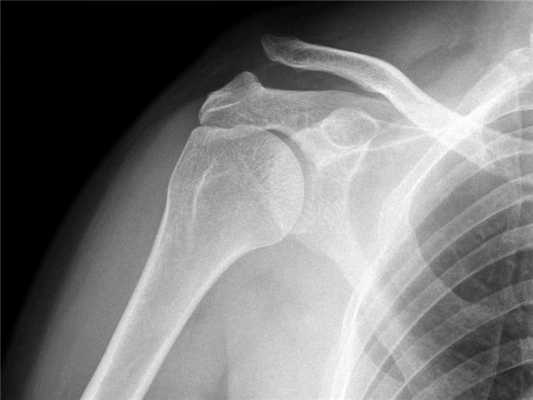

Практически во всех случаях определить получение вывиха ключицы оказывается достаточно легко, с учетом проявляемых клинических признаков. Из дополнительных методов исследования больному может быть назначено проведение рентгеновского исследования. Для правильного установления диагноза, целесообразно выполнять рентгенограмму здорового и больного плеча на одной пленке.

Диагноз вывиха акромиального конца ключицы

Диагноз вывиха акромиального конца ключицы иногда очень прост и все очевидно при осмотре, а иногда приходится решать целую головоломку. Наиболее оптимальным и распространенным способом диагностики является рентгенография. Стоит сказать, что, как не бывает одинаковых людей, так и не бывает одинаковых ключиц. Чаще всего причиной ложного диагноза индивидуальные особенности акромиально-ключичного сустава.

Поэтому целесообразно выполнять рентгенограмму не одного плеча, а двух сразу - что позволит оценить нормальное строение противоположной ключицы.

В сомнительных случаях иногда выполняют функциональную рентгенографию - в руку берут груз, который оттягивает ее вниз и вывих становится более очевидным.

Рентгенография акромиально-ключичных суставов. Вывих акромиального конца левой ключицы (справа норма для сравнения).